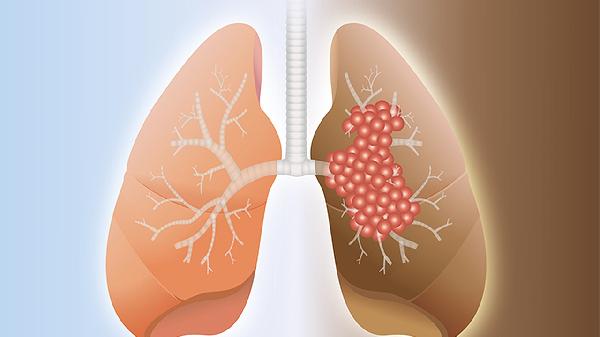

二、为什么肺部问题会反映在手上

1、微循环障碍理论

肺部功能下降会导致血氧交换效率降低,肢体末梢作为供血"最后一公里",最容易出现代偿性血管扩张等异常表现。